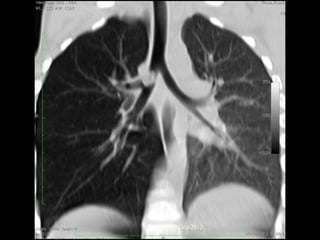

Morphology - Gross  Affects lower lobes  Bilateral  Air passages that are vertical  Tumor/FB aspiration – localized single segment  Severe involvement - more distal bronchi  Airways are 4x dilated than normal CSBRP-Dec-2012

Gross contd…. 1. Cylindrical– most common, tube like dilation 2. Fusiform – spindle shaped dilation. 3. Saccular – sac like distension. 4. Varicose – irregular bronchial enlargement. Cut sections shows HONEY COOMBED appearance. CSBRP-Dec-2012

This is a bronchogram that demonstrates saccular bronchiectasis on the right in the lower lobe. The contrast media fills dilated bronchi, giving a saccular, dilated outline. CSBRP-Dec-2012

Dilatation of Bronchi & Bronchioles 2cms CSBRP-Dec-2012

Bronchiectasis, secondary to obstruction involving the right middle lobe. CSBRP-Dec-2012